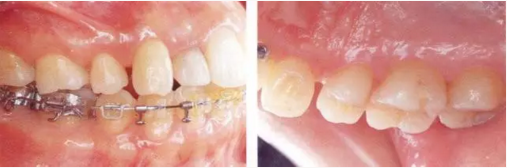

2222.png

▲圖18-1,2

▲圖18-1  左下5佩戴金屬冠,但是由于近遠(yuǎn)中接觸點(diǎn)的位置和大小不合適,導(dǎo)致鼓形間隙基本消失。

▲圖18-2  同部位的X光片??梢钥吹烬l下有牙結(jié)石沉積,并且有牙槽骨吸收現(xiàn)象。